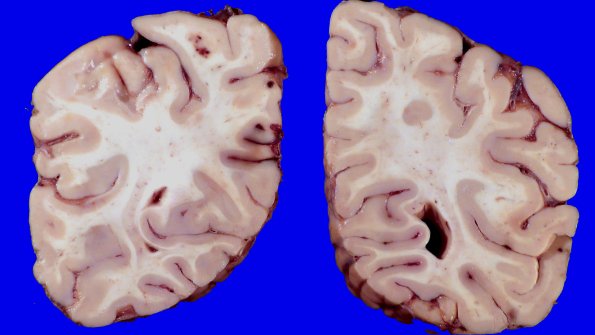

23F4 Infarct tumor embolus (Case 23) 1_4

Additional lesions are illustrated in the cerebral hemispheres.